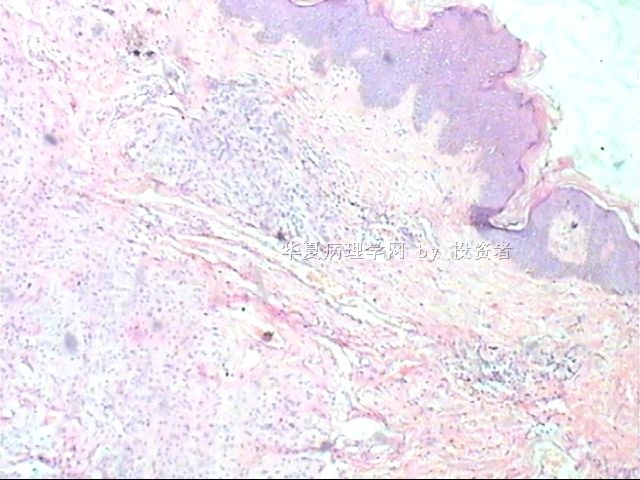

B1634求助皮肤赘生物肿瘤类型

姓    名: ××× 性别:  女 年龄:  25

标本名称: 尾骨下端皮肤赘生物

简要病史:  皮肤赘生物10年余

肉眼检查:  体积1×0.5×0.3cm

×参考诊断

皮内痣

隐约中见似皮内痣。

皮内痣,披着神秘的面纱。

染色太淡,看不清楚。

谢谢各位老师,皮内痣,学习了!

皮内痣可能